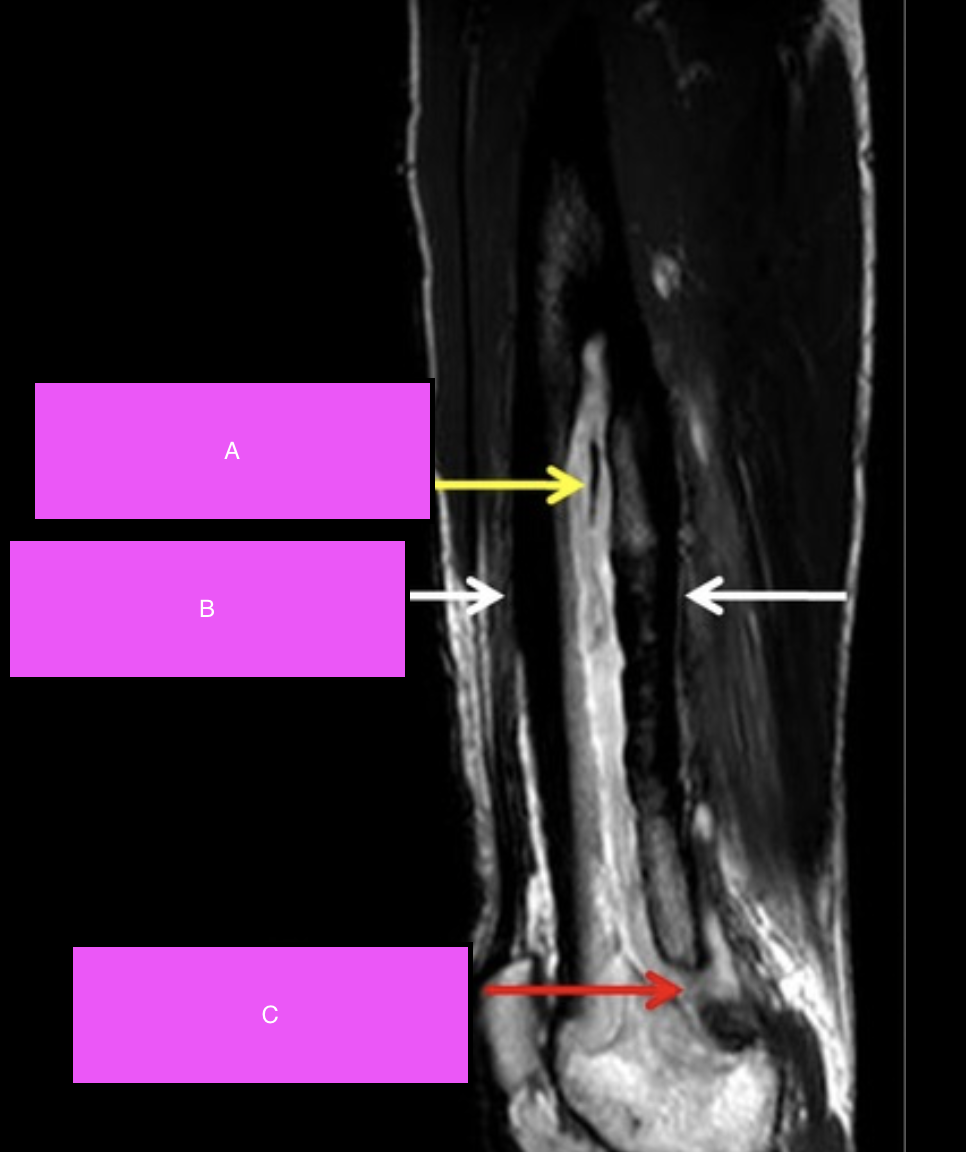

Label A-C

Sequestrum: Refers to a dead piece of devitalised bone that has been separated (i.e. sequestered) due to necrosis from the surrounding bone.

Involucrum: New growth of periosteal bone around a sequestrum.

Cloaca: An opening in an involuvcrum that allows the internal necrotic bone and pus to discharge out.